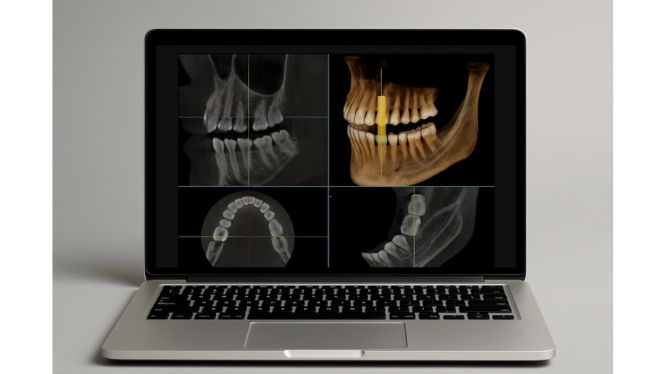

🪛 Cirugía de implantes dentales

¿Además de todo, la colocación de implantes se ha transformado con la tomografía 3D. Hoy, ningún especialista serio coloca implantes sin antes estudiar el caso en CBCT. Las ventajas incluyen:

- Planificación digital del trayecto del implante.

- Elección adecuada del diámetro y longitud.

- Evaluación de densidad ósea.

- Uso de guías quirúrgicas diseñadas digitalmente.

- Precisión protésica: se alinea la cirugía con la rehabilitación.